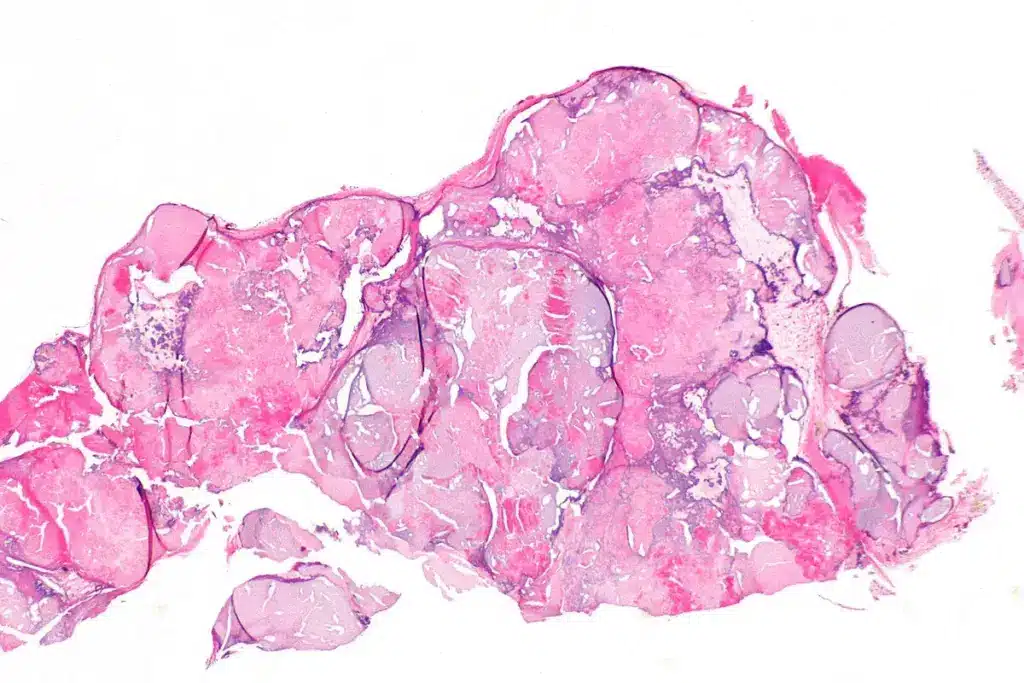

Normal Valve Structure and Tissue Composition

Heart valves are made of strong, flexible tissue. This lets them open and close well. The structure of a normal valve includes:

- Leaflets or Cusps: Thin, fibrous parts that come together to either let or block blood flow.

- Annulus: A ring-like structure that supports the valve leaflets.

- Chordae Tendineae: Fibrous strings that connect the valve leaflets to the papillary muscles. They keep the leaflets from blowing back into the atrium.